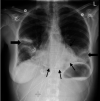

A 44-year-old previously well woman presented with features of respiratory sepsis including a productive cough and fevers, with a recent preceding influenza-like illness. She was diagnosed with community-acquired pneumonia on chest radiograph, influenza infection via nasopharyngeal swab and Streptococcus pneumoniae bloodstream infection with associated purulent pericarditis. She was managed with pericardial drainage and concurrent treatment with antibiotics and made an excellent recovery. This case highlights the complications of both influenza and S. pneumoniae infections, and the importance of prevention via vaccination.